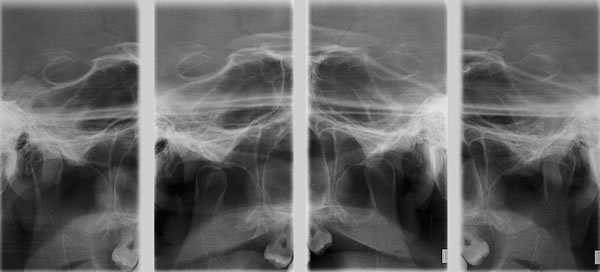

ATM